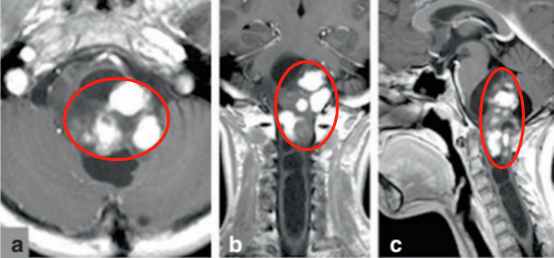

肿瘤从延髓后方悄然生长, 如藤蔓般向下侵犯至颈髓第三椎体(C3)水平。影像上清晰可见:一部分肿瘤组织在造影剂下呈现明显强化,旁边还紧贴着一个无强化的囊性区域。更令人揪心的是,肿瘤的压迫已在脊髓内部撕开了一个空洞,从颈部一路延伸至胸椎第一椎体(T1)。

图a,b,c:肿瘤侵犯延髓-颈髓区域并形成空洞